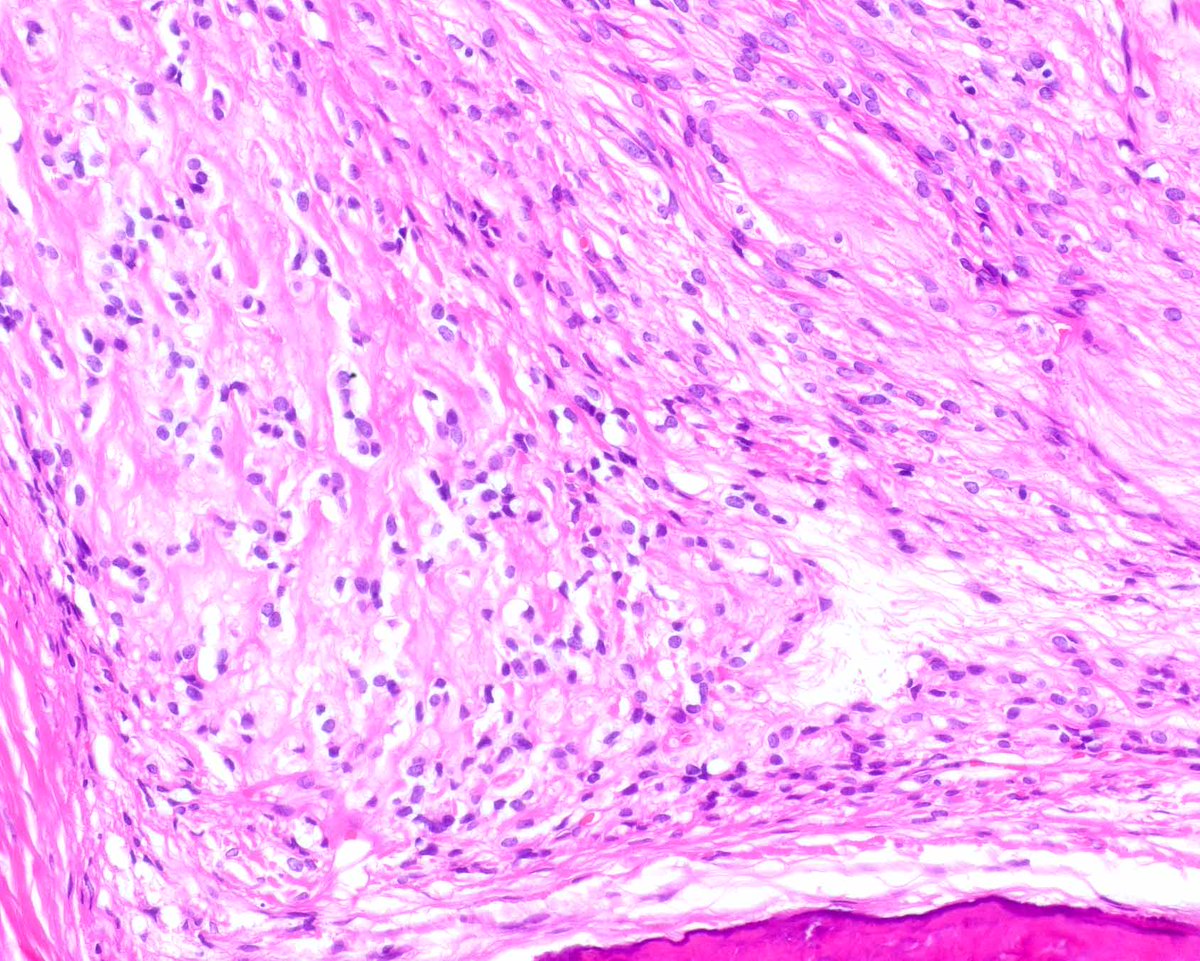

This classic example of ossifying fibromyxoid tumor displays a shell of bone and uniform cytologic features; it's an H&E diagnosis. Without classic features, detecting PFH1 rearrangements (several partner genes reported) is useful. #UMiamiPath PMIDs: PMID: 2476942, 23887158.